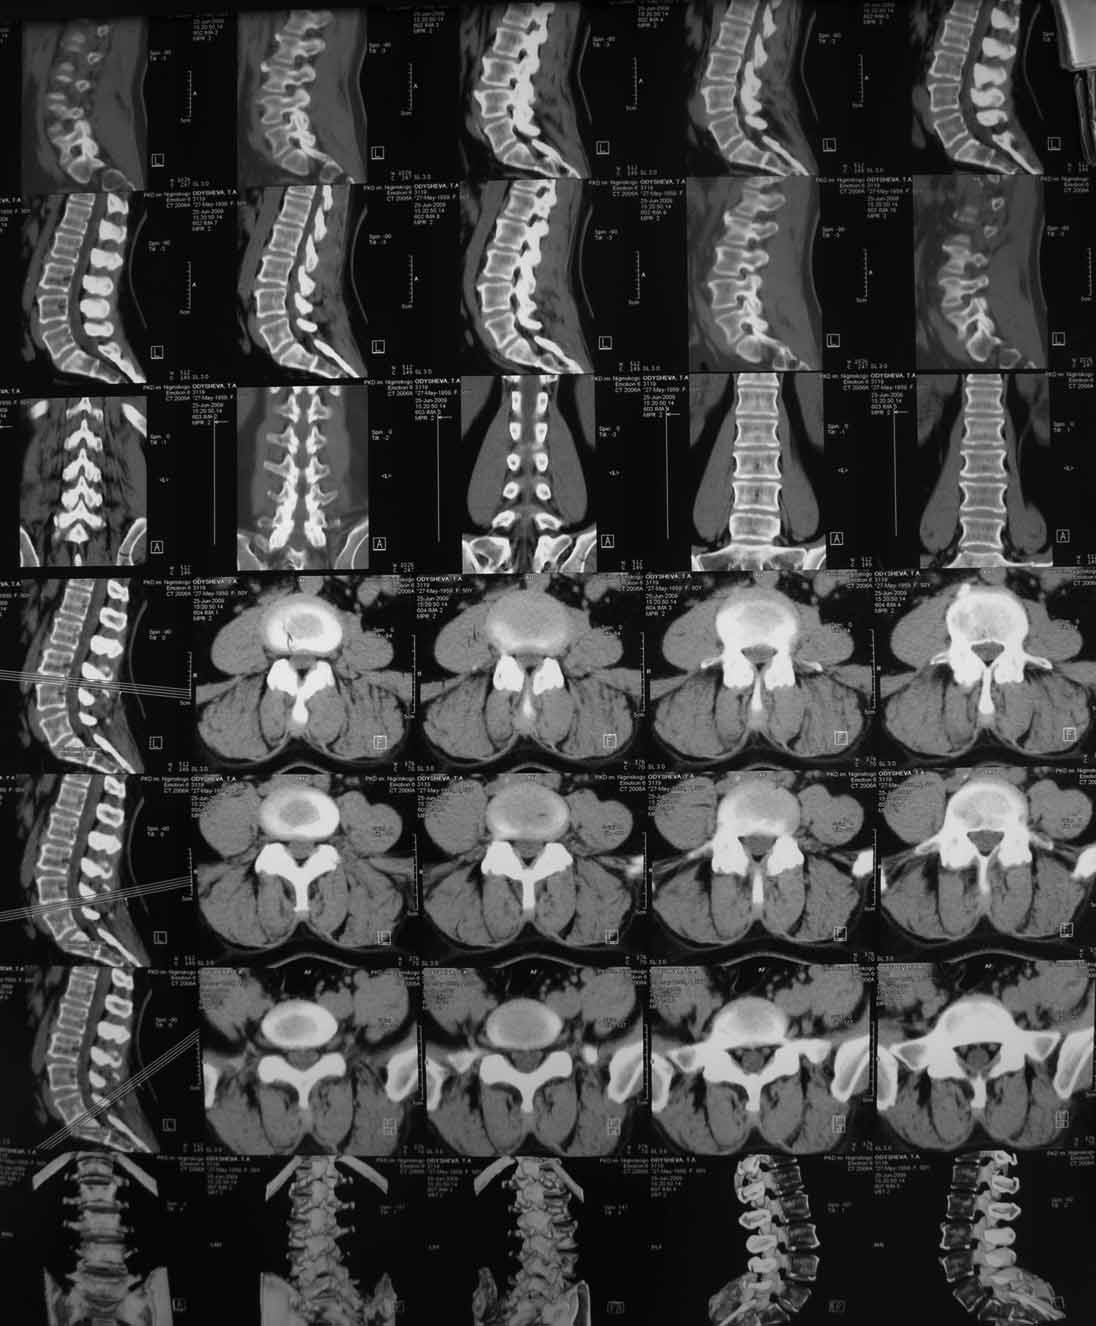

Боли отмечала и раньше, но они беспокоили не сильно, справлялась мазями, отдыхом. В течени последних пяти лет боли выраженного характера, не зависящие от положения тела, усиливающиеся при движениях, при резких движениях и кашле стреляющего характера, не иррадиирую. Ходит с трудом при помощи костылей. Движения ограничены из за боязни боли. Сиптомы натяжения отрицательны. Последние 3 года на инвалидности (была врачем). Неоднократно проходила курсы консервативного лечения по поводу остеохондроза позвоночника (сосудистые препараты, НПВС, всевозможные блокады, массаж)санаторно-куротное лечение с незначительным и очень ограниченным эффектом. На Р-граммах, КТ, МРТ остеохондроз не выраженный, грыж дисков нет. Лечилась у неврологов, консультирована вертебролагами в разных НИИТО.

В 2009г установлен диагноз - сакроилеит справа.На представленных КТ имеется гипертрофия заднего отдела правой подвздошной кости с образованием контакта с задней поверхностью крестца.В январе 2011 года выполнена попытка удаления гипертрофированного участка подвздошной кости. удаленные участки кости исследованы гистологически - губчатая кость с элементами гиалинового хряща. После операции положительного эффекта не получено. На контрольной КТ от 04.2011 обнаружено что, желаемого результата операции не получено(интересующий участок удален частично), при этом имеется расслоение заднего отдела правой подвздошной кости.

На первичных КТ от 19-12-2009 определяется частичное анкилозирование правого крестцово-подвздошного сочленения, а на последних, от 11-04-2011 протяженность анкилозированной зоны значительно больше - сакроилеит прогрессирует, (с левой стороны вроде тоже признаки сакроилеита появились - не очень понятно из-за качества снимка). Значимых дуральных и радикулярных конфликтов действительно нет. "расслоение кости" - рентгенологически выглядит как травматический перелом подвздошной кости. Что делать? - наверное, искать серонегативные спондилоартропатии у ревматолога.